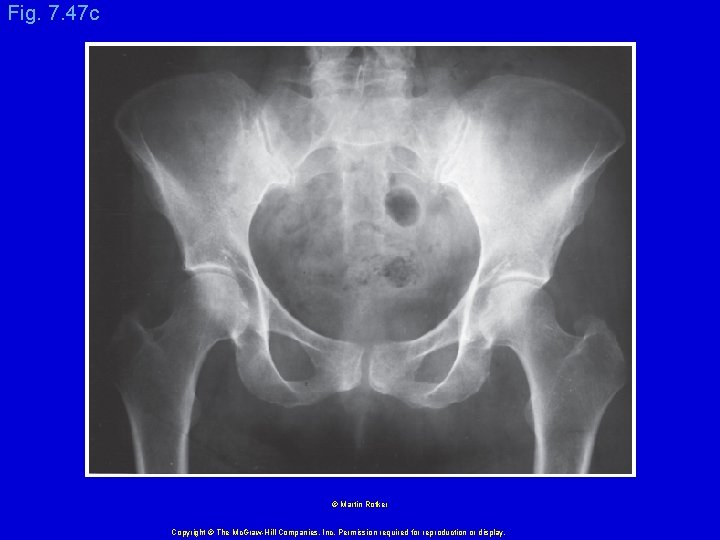

Fig. 7. 47 c © Martin Rotker Copyright © The Mc. Graw-Hill Companies, Inc. Permission required for reproduction or display.